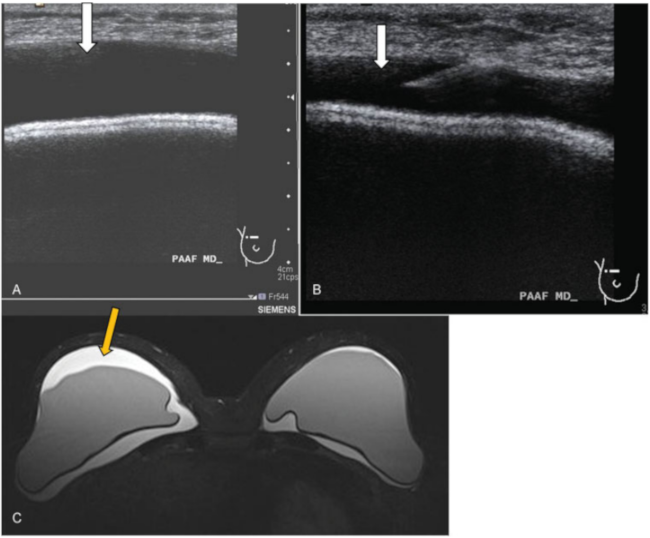

Es una entidad muy rara, existiendo aproximadamente 200 casos publicados, 6 de ellos bilaterales. Se trata de un linfoma de células T asociado a prótesis (CD30-, ALK-). La forma más frecuente de presentación es la de un seroma periprótesis tardío (þ de 1 año), sin otra causa que lo justifique como podría ser traumatismo o infección (►Fig. 11).

Linfoma anaplásico asociado a prótesis. Paciente mujer de 55 años con antecedente de mastectomía bilateral por carcinoma lobulillar in situ. Refirió molestias en ambas mamas, fundamentalmente en el lado derecho. (A) Ecografía. Líquido anecoico periprotésico de nueva aparición, de predominio en el lado derecho (flecha). (B) Se realizó punción aspiración con aguja fina (PAAF) con control ecográfico del líquido (flecha). (C) RM secuencia potenciada en T2 donde se identificó líquido periprotésico bilateral, de predominio en el lado derecho (flecha amarilla) e integridad de las prótesis en secuencias específicas (no incluidas). El resultado citológico de la punción fue de linfoma anaplásico de célula grande asociado a implante mamario.

Su causa es desconocida, aparentemente por una reacción inmunológica exagerada. Para diagnosticarlo es necesario realizar una punción aspiración con aguja fina (PAAF), con control ecográfico y análisis citológico del líquido periprótesis.25 Una vez obtenido ese diagnóstico, el tratamiento adecuado es retirar la prótesis y capsulectomía completa. En la mayoría de casos no es necesario quimioterapia ni radioterapia.

Por tanto, como recomendación, se debe realizar PAAF ante el hallazgo de un seroma periprótesis de inicio brusco sin otra causa que lo justifique, para descartar esa entidad.